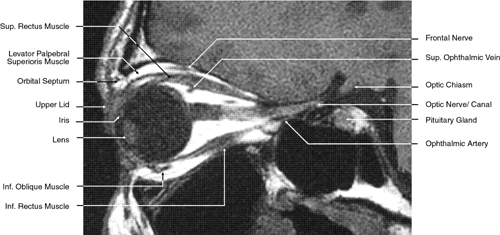

Fig. 26. T1-weighted magnetic resonance imaging; sagittal image through optic nerve.

The orbital roof is approximately triangular and is composed of the frontal bone anteriorly and the lesser wing of the sphenoid posteriorly. The roof is markedly concave, with the greatest degree of this concavity in the area of the equator of the globe (see Fig. 26). At the anterior and lateral portion of the orbital roof lies the lacrimal gland in the lacrimal fossa (see Figs. 18 and 23). This gland consists of a large orbital portion and a smaller palpebral portion. The orbital portion normally measures 20 × 12 × 5 mm, whereas the palpebral portion is about one third of this size.49 The supraorbital notch is at the junction of the nasal third and the lateral two thirds of the bony orbital margin (see Fig. 1). The trochlea of the superior oblique muscle is located 4 mm posterior to the orbital margin in the medial and anterior portion of the orbital roof (see Figs. 17, 24, and 25). Although usually a cartilaginous structure, it is occasionally partially or wholly ossified. It measures 4 × 6 mm and is firmly attached by connective tissue to the periosteum. The frontal bone portion of the orbital roof is extremely thin and like the orbital floor is subject to so-called blow-in fractures as well as to penetrating injury.50 The posterior portion of the roof is more substantial, measuring 3 mm thick. Except for the anterior portion of the orbit, the intracranial cavity lies directly superior to the orbital cavity (see Fig. 26). The levator muscle and the superior rectus muscle just inferior to it are present along the midportion of the orbital roof for all but its most anterior portion (see Fig. 26). The superior oblique muscle, after it changes direction at the trochlea, is present inferior to the anterior portion of the roof and inserts onto the globe inferior to the superior rectus muscle.

Immediately beneath the central portion of the orbital roof lies the frontal nerve, a branch of the ophthalmic division of the trigeminal nerve (see Fig. 18). Along with the trochlear nerve and lacrimal nerve, another branch of the ophthalmic division of the trigeminal nerve, it enters the orbit through the superior orbital fissure superior to the annular tendinous insertions of the extraocular muscles. The lacrimal nerve enters the orbit medial and superior to the superior orbital vein and travels laterally below the orbital roof and superior to the lateral rectus muscle to enter the lacrimal gland (see Fig. 24). The lacrimal artery arises from the ophthalmic artery lateral to the optic nerve and travels with the distal two thirds of the lacrimal nerve. The supraorbital and supratrochlear arteries branch from the ophthalmic artery superior to the optic nerve, passing medially to the superior rectus and levator muscles to accompany the supraorbital and supratrochlear nerves, the two branches of the frontal nerve, as they pass above the levator muscle. The supraorbital vein and artery accompany the nerve along the anterior two thirds of its course before exiting with it at the supraorbital notch. The other branch of the frontal nerve, the supratrochlear nerve, travels medially after separating from the frontal nerve at approximately the junction of the posterior one third and anterior two thirds of the orbit. The trochlear nerve diverges from the frontal nerve in the posterior orbit, passing medially below the orbital roof and above the levator and superior rectus muscles to enter the superior aspect of the posterior half of the superior oblique muscle.